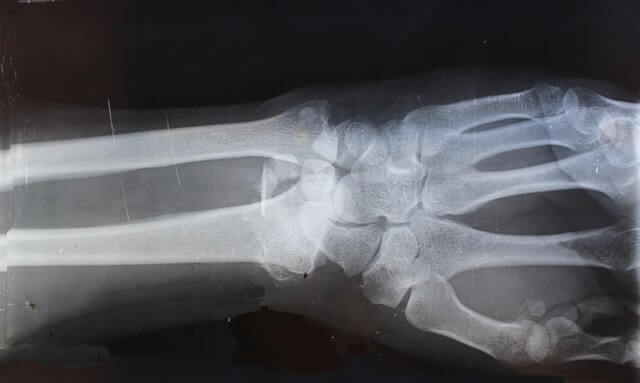

Durchgangsarzt(D-Arzt) zugelassen zu werden. D-Ärzte, die umgangssprachlich auch BG- (Berufsgenossenschaft) Ärzte bezeichnet werden, sind in der Regel Fachärzte für Chirurgie mit Schwerpunkt Unfallchirurgie oder, wie in meinem Fall, Fachärzte für Orthopädie und Unfallchirurgie mit Zusatzbezeichnung “Spezielle Unfallchirurgie”. Neben dieser fachlichen Befähigung müssen auch weitere Anforderungen an Personal, medizinische Apparate und Räumlichkeiten zur Behandlung erfüllt sein. Darüber hinaus fungieren Durchgangsärzte ebenfalls koordinierend: Sie überwachen den Heilungsprozess und sind Schnittstelle zwischen involvierten Krankenhäusern, behandelnden Ärzten, Reha-Kliniken sowie Versicherungen oder Berufsgenossenschaften.

Mein Praxis-Team und ich stellen Ihre Heilung nach einem Unfall – ob auf dem Weg zur Arbeit oder in der Schule – in den Fokus der medizinischen Versorgung: In unseren modernen Räumlichkeiten in Eppendorf behandle ich Sie erstklassig als Ihr Durchgangsarzt in Hamburg! Kontaktieren Sie uns gerne telefonisch